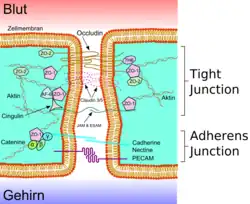

Diese besondere Abgrenzung des Bluts (intravasal) vom extravasalen Raum in Gehirn und Rückenmark ist bei allen Landwirbeltieren (Tetrapoda) ausgebildet und ermöglicht es, für das Nervengewebe eigene Milieubedingungen aufrechtzuerhalten (Homöostase). Im Wesentlichen wird diese Barriere von Endothelzellen gebildet, die hier in den kapillaren Blutgefäßen über Tight Junctions eng miteinander verknüpft sind.

Das wesentliche Element der Blut-Hirn-Schranke bilden die Endothelzellen mit ihren Tight Junctions. Für Funktion sowie Aufbau und Entwicklung der Blut-Hirn-Schranke sind jedoch noch zwei andere Zelltypen, die Perizyten und die Astrozyten, von großer Bedeutung.[1] Die Zell-Zell-Interaktionen zwischen Endothelzellen, Perizyten und Astrozyten sind so eng wie bei sonst keinen anderen Zellen. Diese drei Zelltypen zusammen bilden die Blut-Hirn-Schranke der meisten Wirbeltiere, die endotheliale Blut-Hirn-Schranke.[5][6] Die nachfolgenden anatomischen Angaben beziehen sich auf die endotheliale Blut-Hirn-Schranke der Wirbeltiere. Die bei einigen Wirbeltieren und vielen Wirbellosen ausgebildete gliale Blut-Hirn-Schranke wird am Ende dieses Kapitels gesondert aufgeführt.

Die Tight Junctions

| A Lumen (Biologie) B apikale Seite C basale Seite a Mucus b apikale Seite c basolaterale Oberfläche d Tight Junctions f parazellulärer Raum g Zellmembran | e Proteinkomplex 1 Occludin 2 Claudin-1 3 E-Cadherin 4 ZO-1 5 JAM-1 6 Catenine 7 Cingulin 8 Aktin |

Die Endothelzellen sind über feste Zell-Zell-Verbindungen, die sogenannten Tight Junctions, miteinander verbunden. Diese Tight Junctions stellen dichte Verbindungen zwischen benachbarten Zellen dar und liefern einen wesentlichen Beitrag für die Schrankenfunktion der Blut-Hirn-Schranke.[24][25] Denn sie dichten den Raum zwischen den Zellen ab und schließen so einen parazellulären Transport, die Passage von Stoffen längs des interzellulären Spaltraums zwischen benachbarten Endothelzellen an diesen vorbei, praktisch aus.[26][27][28]

Mehrere Transmembranproteine, wie Occludin, verschiedene Claudine und Junctional Adhesion Molecules (JAM), verknüpfen die Endothelien im apikalen Bereich der lateralen Zellwände durch umlaufende Proteinbänder in Tight junctions, und unterbinden damit die parazelluläre Passage via Zwischenzellspalt zweier Endothelzellen für größere Moleküle weitgehend.[29] Die einzelnen Protein-Protein-Verbindungen wirken wie parallel verschaltete Sicherungen. Die Endothelzellen der Blut-Hirn-Schranke exprimieren von den 24 bekannten Claudinen nur Claudin-5 und Claudin-12. Claudin-5 wird dabei als wichtigstes Zelladhäsionsprotein der Blut-Hirn-Schranke angesehen.[30] Das Ausschalten (Gen-Knockout) des CLDN5-Gens, das für Claudin-5 codiert, führt bei Mäusen dazu, dass die Blut-Hirn-Schranke für Moleküle mit einer molaren Masse von bis zu 800 g·mol−1 durchlässig wird. Die so genetisch veränderten Tiere verstarben innerhalb weniger Stunden nach ihrer Geburt.[31]

Durch die Fixierung der Endothelien wird zugleich deren Ausrichtung in zwei sehr unterschiedliche Seiten gewährleistet: in die luminale, dem Blut entgegengerichtete Seite und die abluminale, dem Gehirn zugewandte Seite.[6]